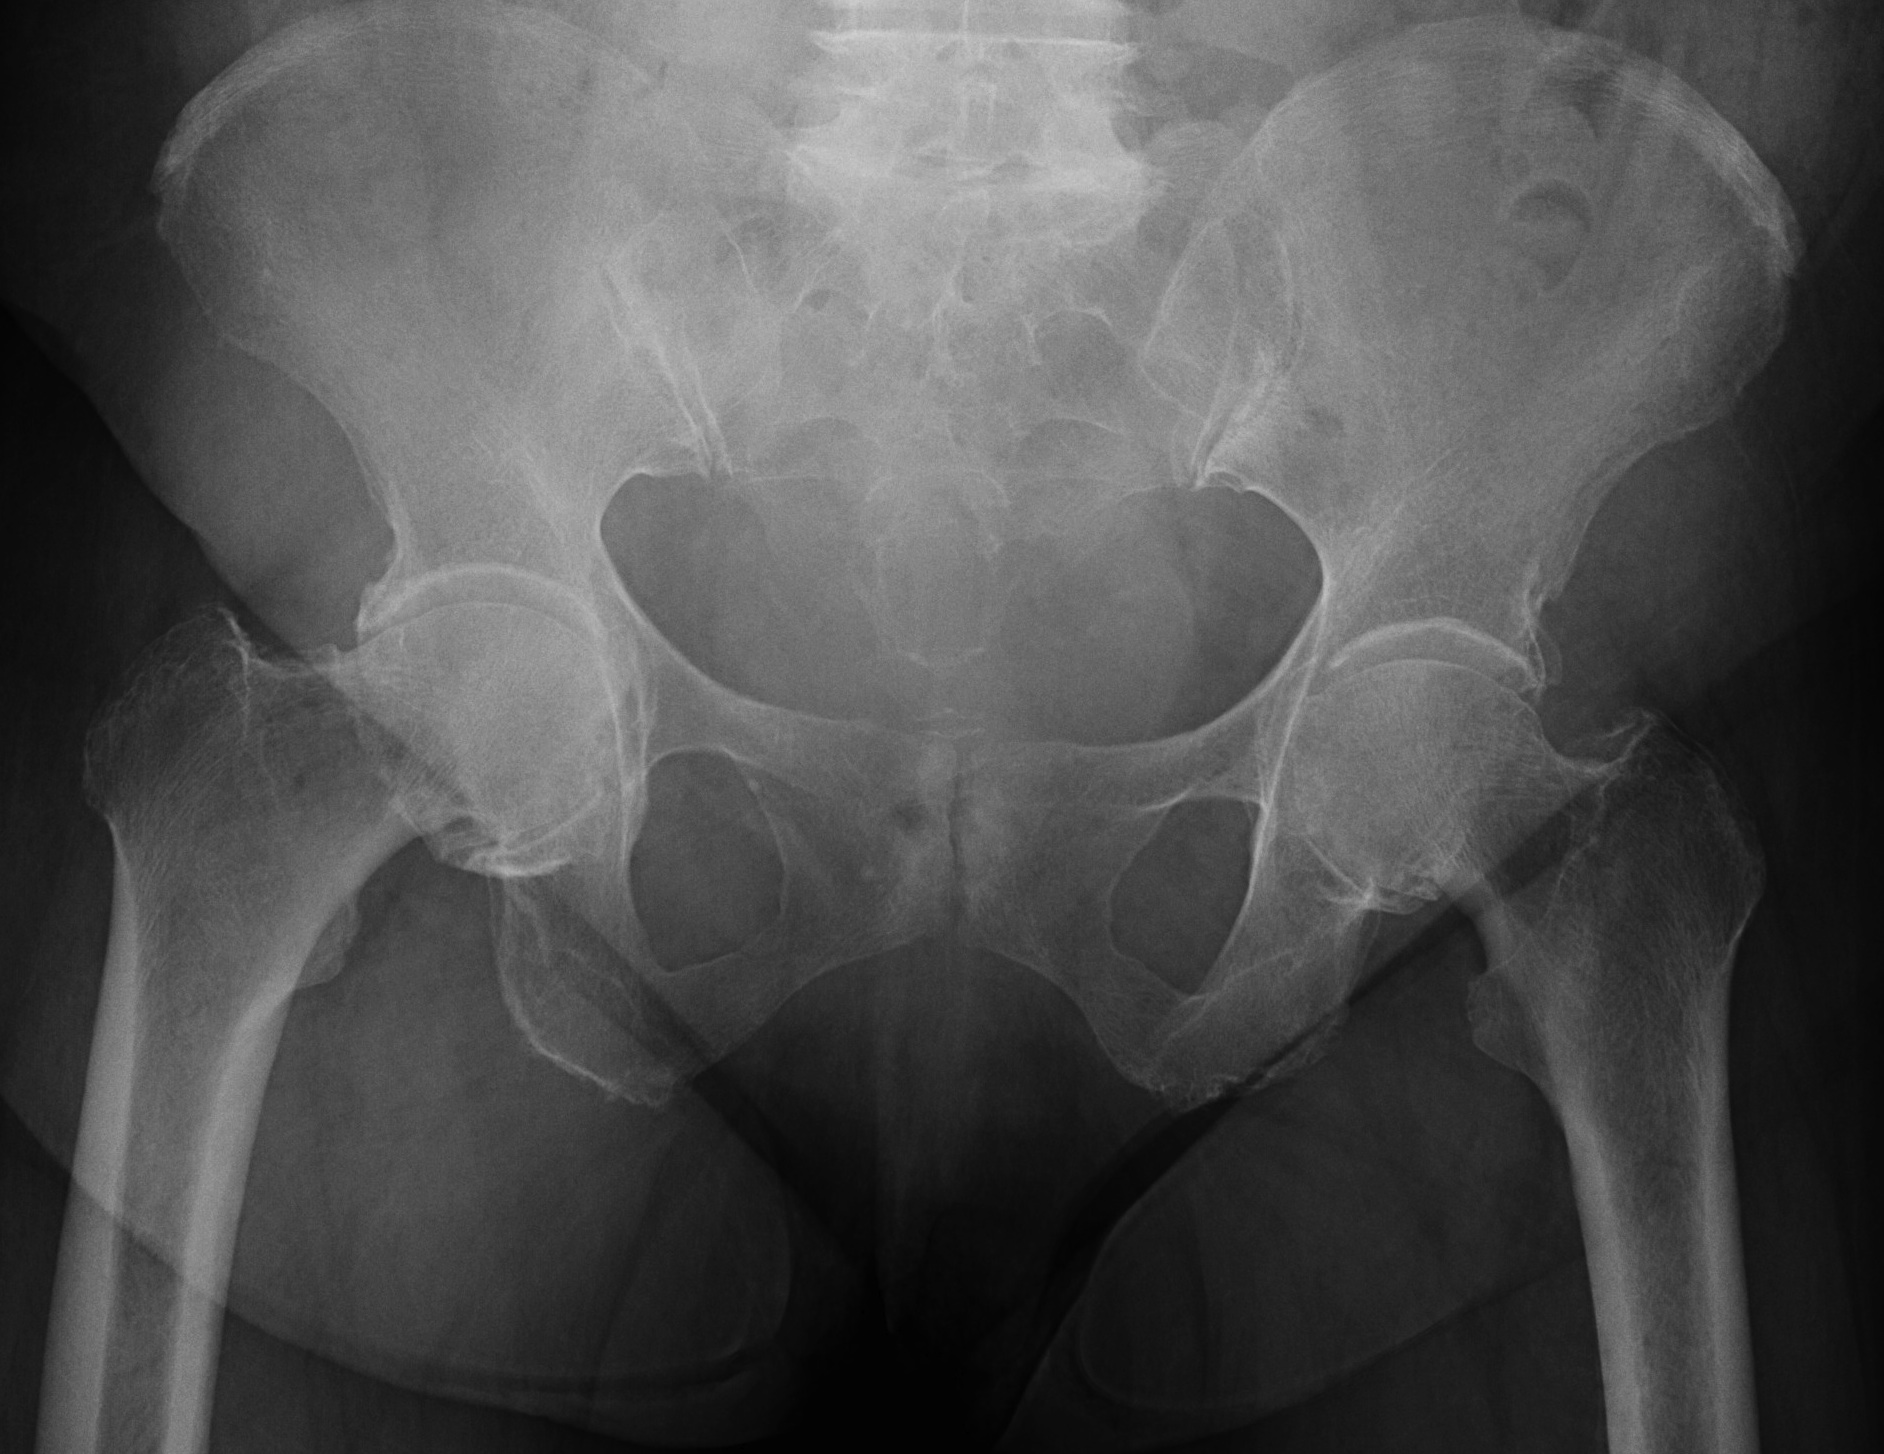

Radiology

Inverted Y

- inferior sclerotic metaphyseal triangle

- pathognomonic of developmental

Varus femoral neck

- neck-shaft angle < 125° (normal is 150° in infant)

- difficult to define with severe disease

Hilgenreiner's Epiphyseal angle

- angle between Hilgenreiner's & Physeal line

- normal < 25°

- < 45° should resolve

- 45-60° - watch

- > 60° will progress

Also

- decreased femoral anteversion / retroversion

- coxa breva